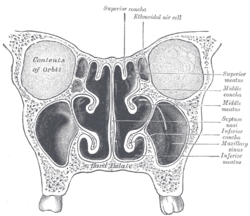

Horizontal section of nasal and orbital cavities.

Coronal section of nasal cavities.